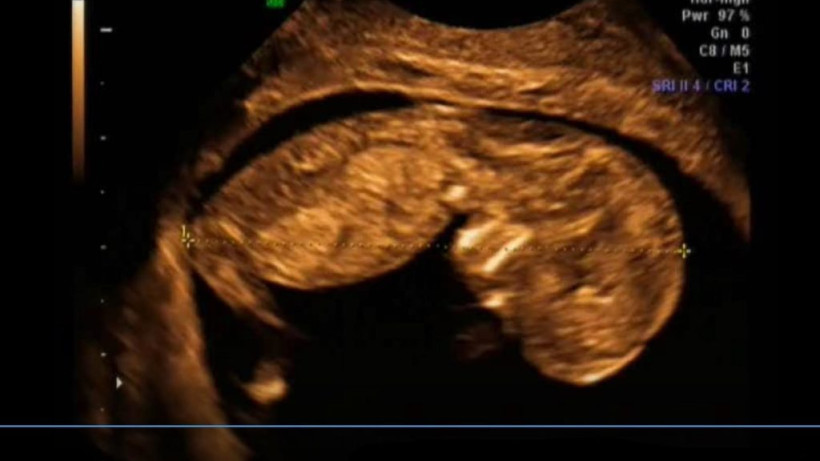

W 11. tygodniu życia wszystkie narządy dziecka są już ukształtowane. Ich doskonalenie jednak trochę jeszcze potrwa. Maleństwo ćwiczy nowe ruchy i staje się coraz sprawniejsze.

Dziecko ma już 6,5

W 12. tygodniu życia Twoje dziecko ćwiczy wytrwale jak sportowiec. Ale potrafi też płakać!

Maleństwo mierzy 7,5 cm długości i waży 14 g. Jest wielkości średniego jabłka.